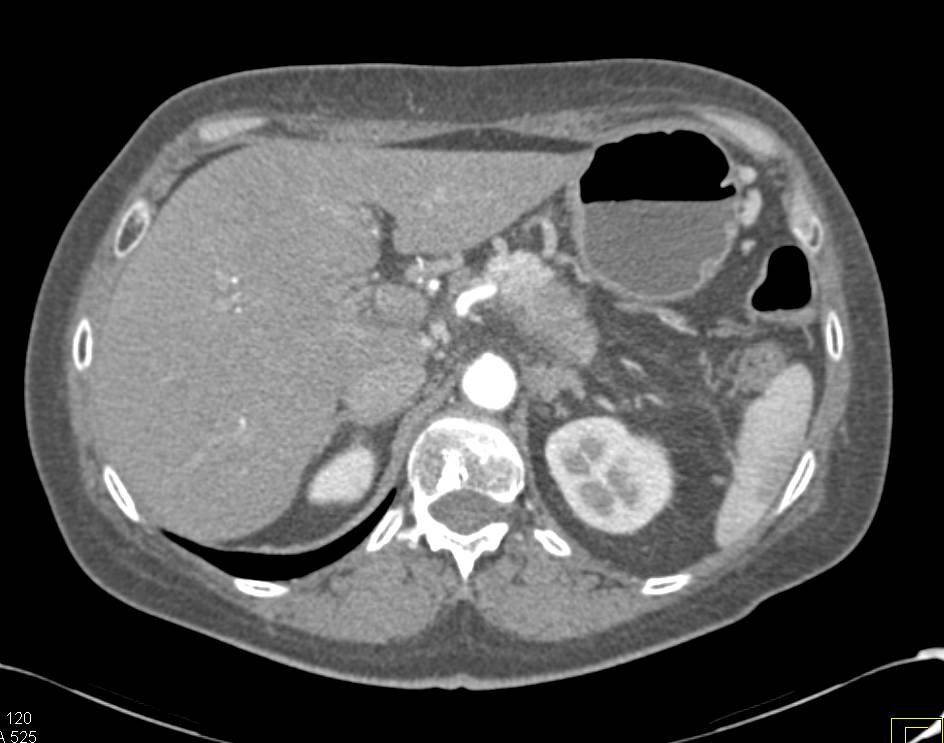

Incidental Pulmonary Embolism (PE) in the Pulmonary Artery to Right Lower Lung in a Patient with Metastatic Pancreatic Cancer